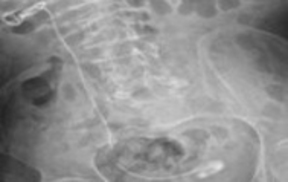

Ender Cem Bulut, Mahmut Uğurlu, Mustafa Kaba

Double-J (DJ) stents are essential tools in various urological

procedures []. With the increasing frequency of DJ stent use,

stent-related morbidities have become more prevalent. In the

short term, complications such as pain, irritation, infection, and

hematuria may occur. In the long term, serious complications

including encrustation, urolithiasis, stent migration, fracture,

renal damage, and even death have been reported []. DJ

stents may require removal through extracorporeal shock

wave lithotripsy (ESWL), cystolithotripsy, laser lithotripsy,

percutaneous nephrolithotomy (PNL), open surgery, or

combinations of these approaches [].

Cerebral palsy (CP) is a neurological disorder affecting

motor function and is frequently associated with urological

complications, particularly lower urinary tract dysfunction [].

The management of urolithiasis in patients with CP is often

challenging due to physical disabilities, anatomical variations,

and accompanying comorbidities [].

Fractured DJ stents are rare clinical occurrences. In this case

report, we present the endourological management and singlesession

removal of a severely encrusted DJ stent that remained

in situ for approximately 2.5 years.